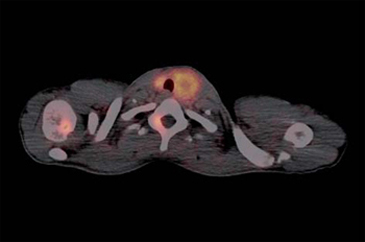

El tumor medular de tiroides es una neoplasia poco frecuente (3-5% de todos los cánceres de tiroides) proveniente de las células C parafoliculares (Figuras 6 y 7). La mayoría ocurre en forma esporádica (70-80% de los casos) pero existen formas familiares (solos o como parte del síndrome NEM 2A y 2B)20. Este tumor metastiza precozmente a los ganglios cervicales (55-75% de los casos), principalmente el compartimiento central del cuello. Metástasis a distancia se encuentran en 10-15% de los pacientes, principalmente mediastino, pulmones, hígado y hueso21 (Figuras 8 y 9). Debido a la producción de calcitonina por las células C, esta hormona es usada como marcador tumoral al diagnóstico y durante el seguimiento. La resección quir úrgica completa (tiroidectomía total y disección cervical amplia) es la únicaforma de curación. A pesar de la agresividad de este tratamiento, 40% de los pacientes operados mantienen niveles de calcitonina medibles y otro 10% inicialmente negativo, recurrirá en el tiempo2. Por esta razón, la localización de cualquier cúmulo tumoral existente mediante imágenes es de extrema importancia. Los criterios usados en imágenes diagnósticas para el tumor primario son similares a los usados en el cáncer diferenciado de tiroides, sin embargo, la localización de adenopatías y metástasis a distancia es generalmente difícil22. Convencionalmente se ha usado ecografía, tomografía computada y cintigrafía (In111-pentatreotide, Tc99m-DMSA- V y Tc99m-MIBI) para evaluar pacientes con enfermedad recurrente. Tc99m(V)-DMSA (ácido dimercaptosuccínico pentavalente) es un marcador tumoral inespecífico. El mecanismo de captación es sólo parcialmente conocido y tendría relación con la presencia de grupos fosfatos y el pH del medio. Su uso en esta enfermedad fue descrito por primera vez en 1984 por Ohta23. La sensibilidad reportada de la cintigrafía con DMSA-V se encuentra entre 50-80% y su uso combinado con In111- pentatreotide alcanza 86%24. F18-FDOPA es un aminoácido (dihidroxifenilalanina) marcado con Flúor18 usado originalmente para el estudio de pacientes con enfermedad de Parkinson. Los tumores neuroendocrinos pueden captar y decarboxilar p recursores de aminoácidos tales como la DOPA y ser visualizados con PETFDOPA. Las series reportan sensibilidades entre 44 y 90% para este método2. Desafortunadamente para la síntesis de F18-FDOPA se requiere de blancos especiales en el ciclotrón (diferentes a los usados para la producción de FDG) y de módulos de síntesis dedicados, lo que hace que este radiofármaco aún no esté disponible en nuestro medio. Si bien el 85% de los tumores medulares de tiroides expresan algún tipo de receptores de somatostatina y 75% expresan los tipos 2,3 ó 5 (que son los afines por octreotide), el subtipo 2 es expresado sólo en 43%25, que es el blanco principal de los análogos disponible para imagen y terapia. La afinidad de estas moléculas por los subtipos 3 y 5 es típicamente menor. Esto explica la variabilidad de resultados en la literatura en relación con la sensibilidad tanto de la cintigrafía con In111-pentatreotide (Octreoscan) como para el PET con derivados de la somatostatina para la detección de esta neoplasia. Las series publicadas con In111-pentatreotide reportan sensibilidades entre 50-75% para cáncer medular de tiroides y sugieren que este método es mejorpara metástasis ganglionares en el cuello o mediastino que para metástasis a distancia2. Estudios con PET y análogos de somatostatina son escasos para esta enfermedad. La limitada información disponible sugiere que la sensibilidad de PET-análogos de somatotatina es inferior al PET-FDOPA en cáncer medular de tiroides tanto a nivel de paciente como de lesión y similar a los resultados de estudios realizados con PET-FDG. En el trabajo retrospectivo de Conry et al2, se estudiaron 18 pacientes con recidiva de cáncer medular de tiroides a los que se le realizó PET con Ga68-DOTATATE y F18-FDG. La sensibilidad encontrada por paciente fue 72% para DOTATATE y 78% para FDG. FDG encontró 28 metástasis mientras que DOTATATE 23. Treglia et al26 recientemente publicó una serie prospectiva de 18 pacientes con recurrencia de cáncer medular de tiroides estudiados PET y Ga68-análogos de somatostatina, F18-FDOPA y F18-FDG. En este trabajo la sensibilidad por paciente fue 72% para FDOPA, 33% para análogos de somatostatina y 17% para FDG. A nivel de lesiones la sensibilidad fue: 85% para FDOPA, 20% para análogos de somatostatina y 28% para FDG.